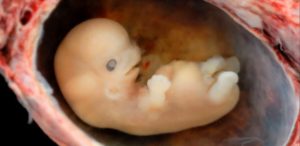

Часто замершая беременность случается в первом триместре на 7–8 неделях.

На этом сроке плод развивается стремительно, матка увеличивается, что вызывает болевые ощущения у женщины. Также болит поясница. В том случае, если боли схваткообразные стоит обратиться к врачу.

Специалисты определили, что некоторые сроки беременности являются особо опасными для малыша, поскольку в это время он особенно уязвим. Такими названы 3-4 недели, 8-11 недели и 16-18 недели беременности. Один из самых критических периодов, когда существует наибольшая вероятность замирания, признана 8 неделя, когда у малыша формируются жизненно важные органы.